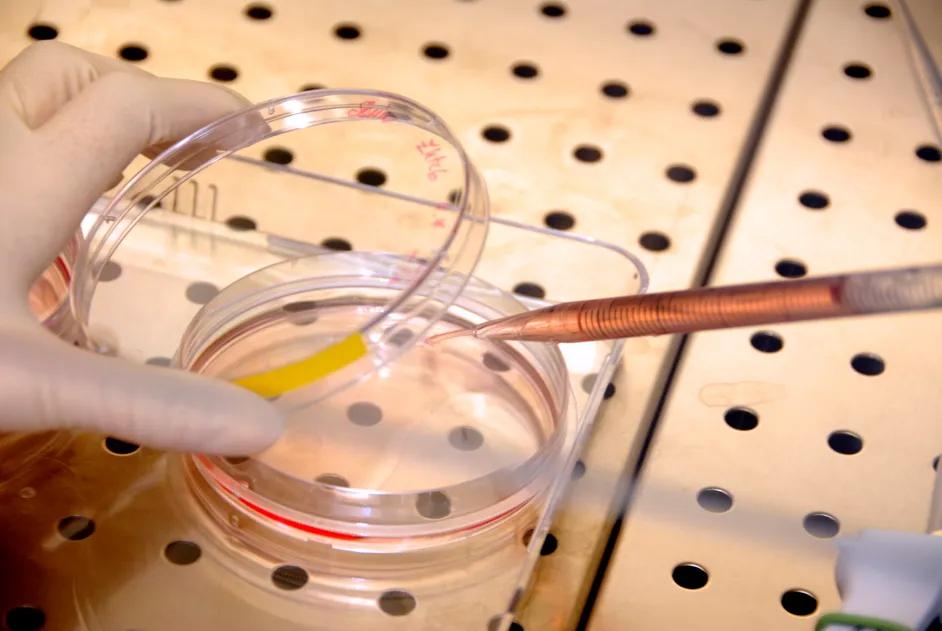

Du 4 au 30 novembre, l’AFM-Téléthon et l’Association des professeurs de biologie et de géologie (APBG) s’associent pour faire entrer le monde de la recherche dans les collèges et lycées. Les élèves vont ainsi pouvoir découvrir les dernières avancées de la recherche biomédicale et le quotidien d’un chercheur !

Du 4 au 30 novembre, l’AFM-Téléthon et l’Association des professeurs de biologie et de géologie (APBG) s’associent pour faire entrer la recherche dans les collèges et lycées.